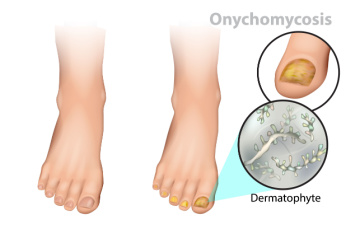

Treating Toenail Fungus

Fungal infection of the toenail, or onychomycosis, typically appears as a gradual change in a toenail’s texture and color that involves brittleness and darkening. The fungal infection itself occurs beneath the surface of the nail. Aside from discoloration, other symptoms include the collection of debris beneath the nail plate, white marks on the nail plate, and a foul odor emanating from the nail. If ignored, the infection can spread into other nails and the skin; in severe cases, it can hinder one’s ability to work or walk.

The toenails are particularly vulnerable to contracting infection in moist environments where people are likely to be walking barefoot, such as around swimming pools, public showers, and locker rooms. Fungal infection may also be more likely to occur in nail beds that have been injured, and sufferers of chronic diseases such as diabetes, circulatory problems, or immunodeficiency conditions are particularly prone to developing fungal nails.

Fungal nails can be primarily prevented by practicing proper hygiene and regularly examining the feet and toes. Carefully washing the feet with soap and water and thoroughly drying the feet afterwards are essential. Other tips include wearing shower shoes in public areas, changing shoes and socks daily, keeping toenails clipped at a short length, wearing breathable shoes that fit properly, wearing moisture-wicking socks, and disinfecting home pedicure tools and instruments used to cut nails.

Fungal nail treatment may vary between patients and the severity of the condition. Your podiatrist may suggest a daily routine of cleansing that spans over a period of time to ease mild infections. Over-the-counter or prescription antifungal agents may also be prescribed, including topical and/or oral medications. Debridement, or the removal of diseased nail matter and debris, may also be performed. In more severe cases, surgical treatment may be needed. In some instances, the temporary removal of the fungal nail allows for the direct application of a topical antifungal to the nail bed. In other cases, a chronically painful fungal nail that has not responded to other treatments may be permanently removed; this allows the infection to be cured and avoids the growth of a deformed nail.

The Progression of Toenail Fungus

Toenail fungus often develops in distinct stages, progressing gradually if left untreated. Initially, it may appear as a small white or yellow spot under the nail tip. As the infection advances, the nail may thicken and take on a yellowish hue, spreading deeper into the nail bed. Without intervention, the fungus continues its relentless progression, causing the nail to become brittle and crumble at the edges. As the infection worsens, the nail may darken in color, emitting a foul odor, and detachment from the nail bed becomes a possibility. This advanced stage not only affects the appearance of the nail but also brings discomfort and potential complications. Recognizing the signs early on is essential for effective treatment. Consulting a podiatrist for proper diagnosis and guidance is necessary to halt the progression and prevent further damage. If you notice toenail fungus developing, it is suggested that you visit a podiatrist who can prescribe medication for a complete healing.